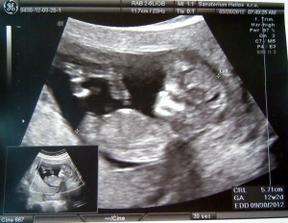

26.3. ultrazvuk NT+ - miminko v pořádku - 13+1tt měříme 69,5 mm a podle paní dr. čekáme chlapečka akrobata